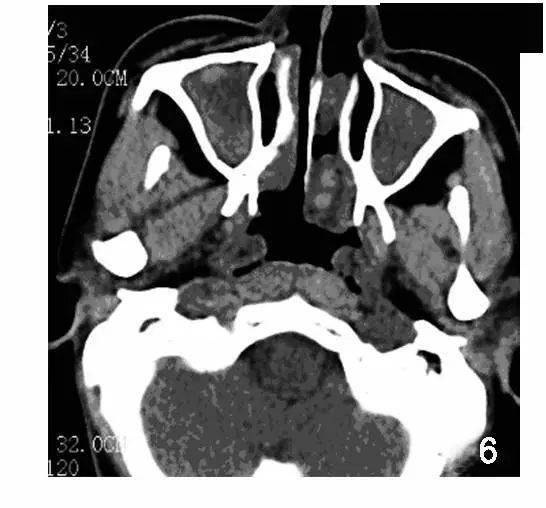

鼻旁窦 CT:全组副鼻窦炎 , 左侧鼻腔斑片状软组织密度影 , 右侧下鼻甲肥厚 。 (图源:参考文献 2 , 非本病例)